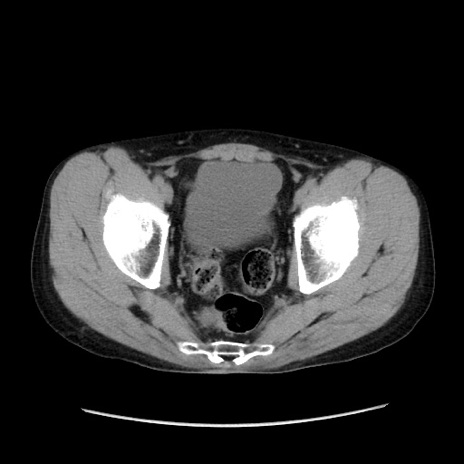

症例37(横断像)

【症例】40歳代 男性

【主訴】腹痛

【現病歴】4時間ほど前に電車に乗車中に臍部上より腹痛出現。徐々に増悪し起立困難となり、救急外来受診。生ものは数日食べていない。今朝お雑煮を食べた。

【身体所見】BT 36.8℃、BP 117/84mmHg、HR 91/min、SpO2 97%、苦悶様、腹部:臍上部広範囲圧痛あり、反跳痛±

【データ】WBC 8100、CRP 0.03